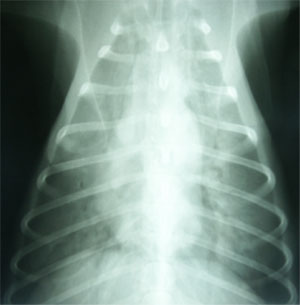

治療および経過:酸素室管理とし、まずフロセミド2mg/kg IM q1hを2回、次にコハク酸メチルプレドニゾロン125mgIVを1回投与したが、ともに反応せずびまん性肺胞浸潤影は次第に悪化した。治療開始8時間を経過してもPao2 46 mmHgにて改善みられず、スパンカー?(パーカッションネア・ジャパン株式会社、東京)を用いたIPV療法を試みた。呼吸ヘッドに酸素マスクを取り付け、操作圧25psi、パーカッションレベルはHardに設定した。処置台上に犬座姿勢を保ち、飼い主を含めた2人に保定してもらった。治療者は呼吸ヘッドを右手で保持しマスクを口吻部に密着するように当てながら、肺内パーカッションを始めた(図2)。後肢の趾間にSpo2のプローブを設置し連続的に経皮的酸素飽和度を観察した。治療直前にはSpo2は69%を示したが、1〜2分で92%にまでただちに上昇した。一回に15〜60秒程度パーカッションを継続した。初日に30分間を7回、2日目に20分2回行った。2日目の朝にPao2 77 mmHg、3日目は IPV実施せずともPao2 94 mmHgと正常化し、びまん性肺胞浸潤影もほぼ消失し(図3)全身状態も改善し退院となった。3週間後、気管支鏡検査により好酸球性肺炎であることが判明した。

図3 治療開始3日目の胸部X線DV像。肺胞浸潤影はほぼ消失した。このときPao2 94 mmHgと正常化し全身状態も改善した。